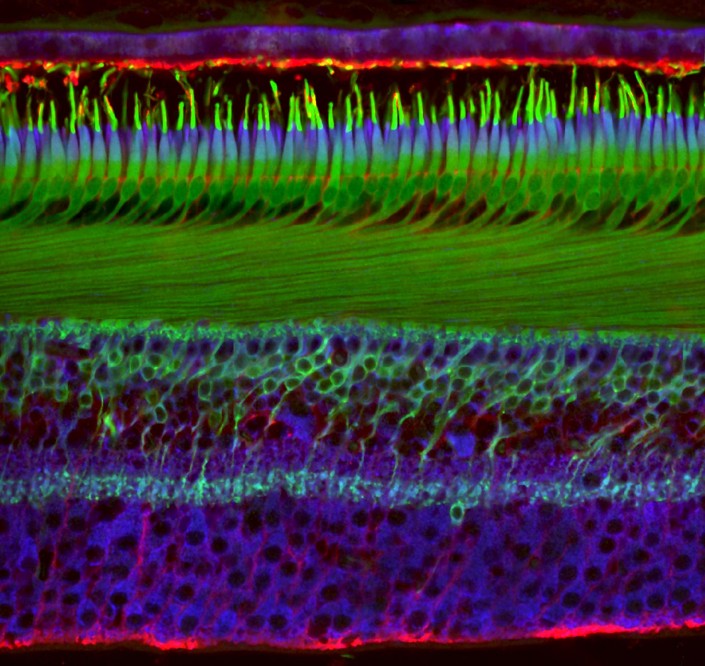

6-е место. Фовеола (область сетчатки глаза) примата, 40-кратное увеличение.

Ханен Хабу, Институт зрения, Франция